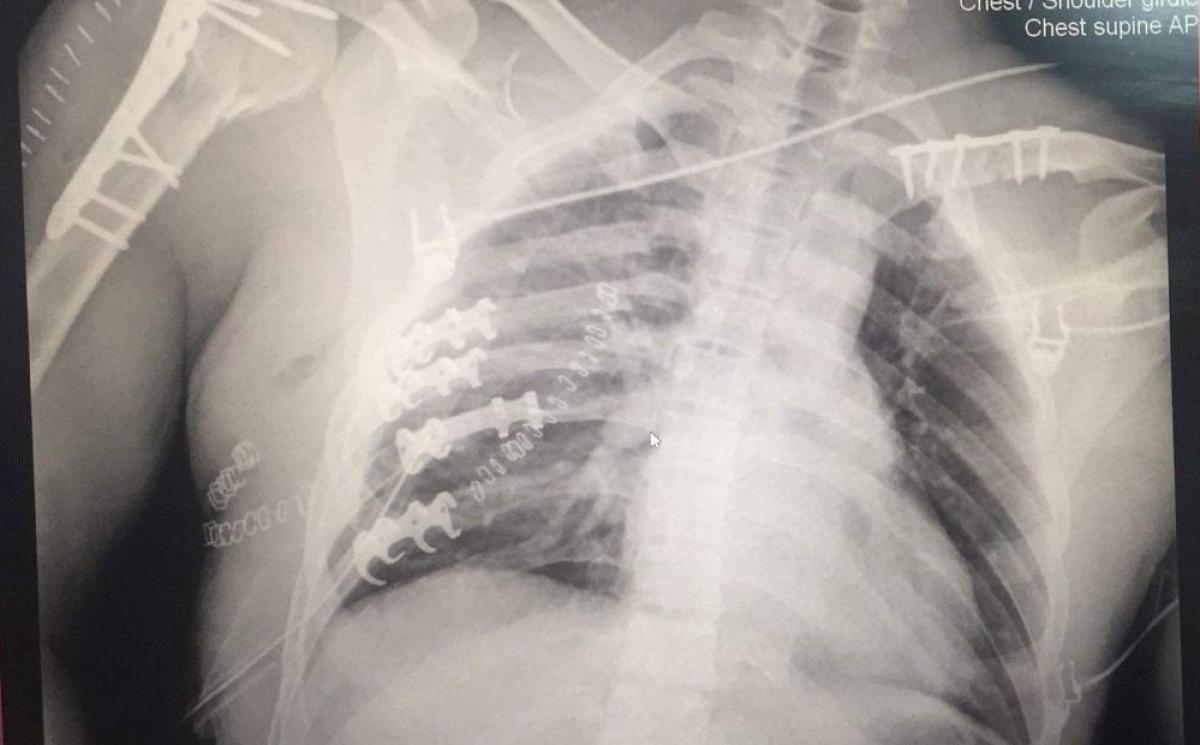

Гэмтэл согог судлалын үндэсний төвийн алсын дуудлагын баг энэ сарын 02-ны өдөр Говь-Алтай аймагт ажиллаж, гар сарвуу дээд мөчдийн гэмтэл болон цээжний хөндийн битүү гэмтэл, хавирганы тогтворгүй хугарал хавсарсан хүнд өвчтөнд мэс заслын яаралтай тусламж үйлчилгээ үзүүллээ.

Тус баг бүрэлдэхүүнд ГССҮТ-ийн Хавсарсан гэмтлийн мэс заслын тасгийн эрхлэгч П.Баярсайхан, Гар сарвуу бичил мэс заслын тасгийн эмч Д.Даваажаргал, Мэс заслын тасгийн сувилагч С.Дорж, жолооч И.Сүхбат багтсан бөгөөд Говь-Алтай аймгийн Нэгдсэн эмнэлгийн Мэс заслын тасгийн их эмч, Монгол Улсын гавьяат эмч Л.Гантөмөр, Гэмтлийн тасгийн эмч Ш.Дагва, Б.Ганхүрэл, Б.Баатарцогт, мэдээгүйжүүлэгийн эмч Т.Санчир-Од болон сувилагч н.Бадмаа, н.Бямбажав, н.Ундармаа, асрагч н.Баасанжаргал нартай хамтран мэс засал эмчилгээг амжилттай хийсэн байна.

Өдгөө өвчтөний биеийн байдал тогтворжиж, Эрчимт эмчилгээний тасагт мэс заслын дараах эмийн эмчилгээ хийлгэж байна.